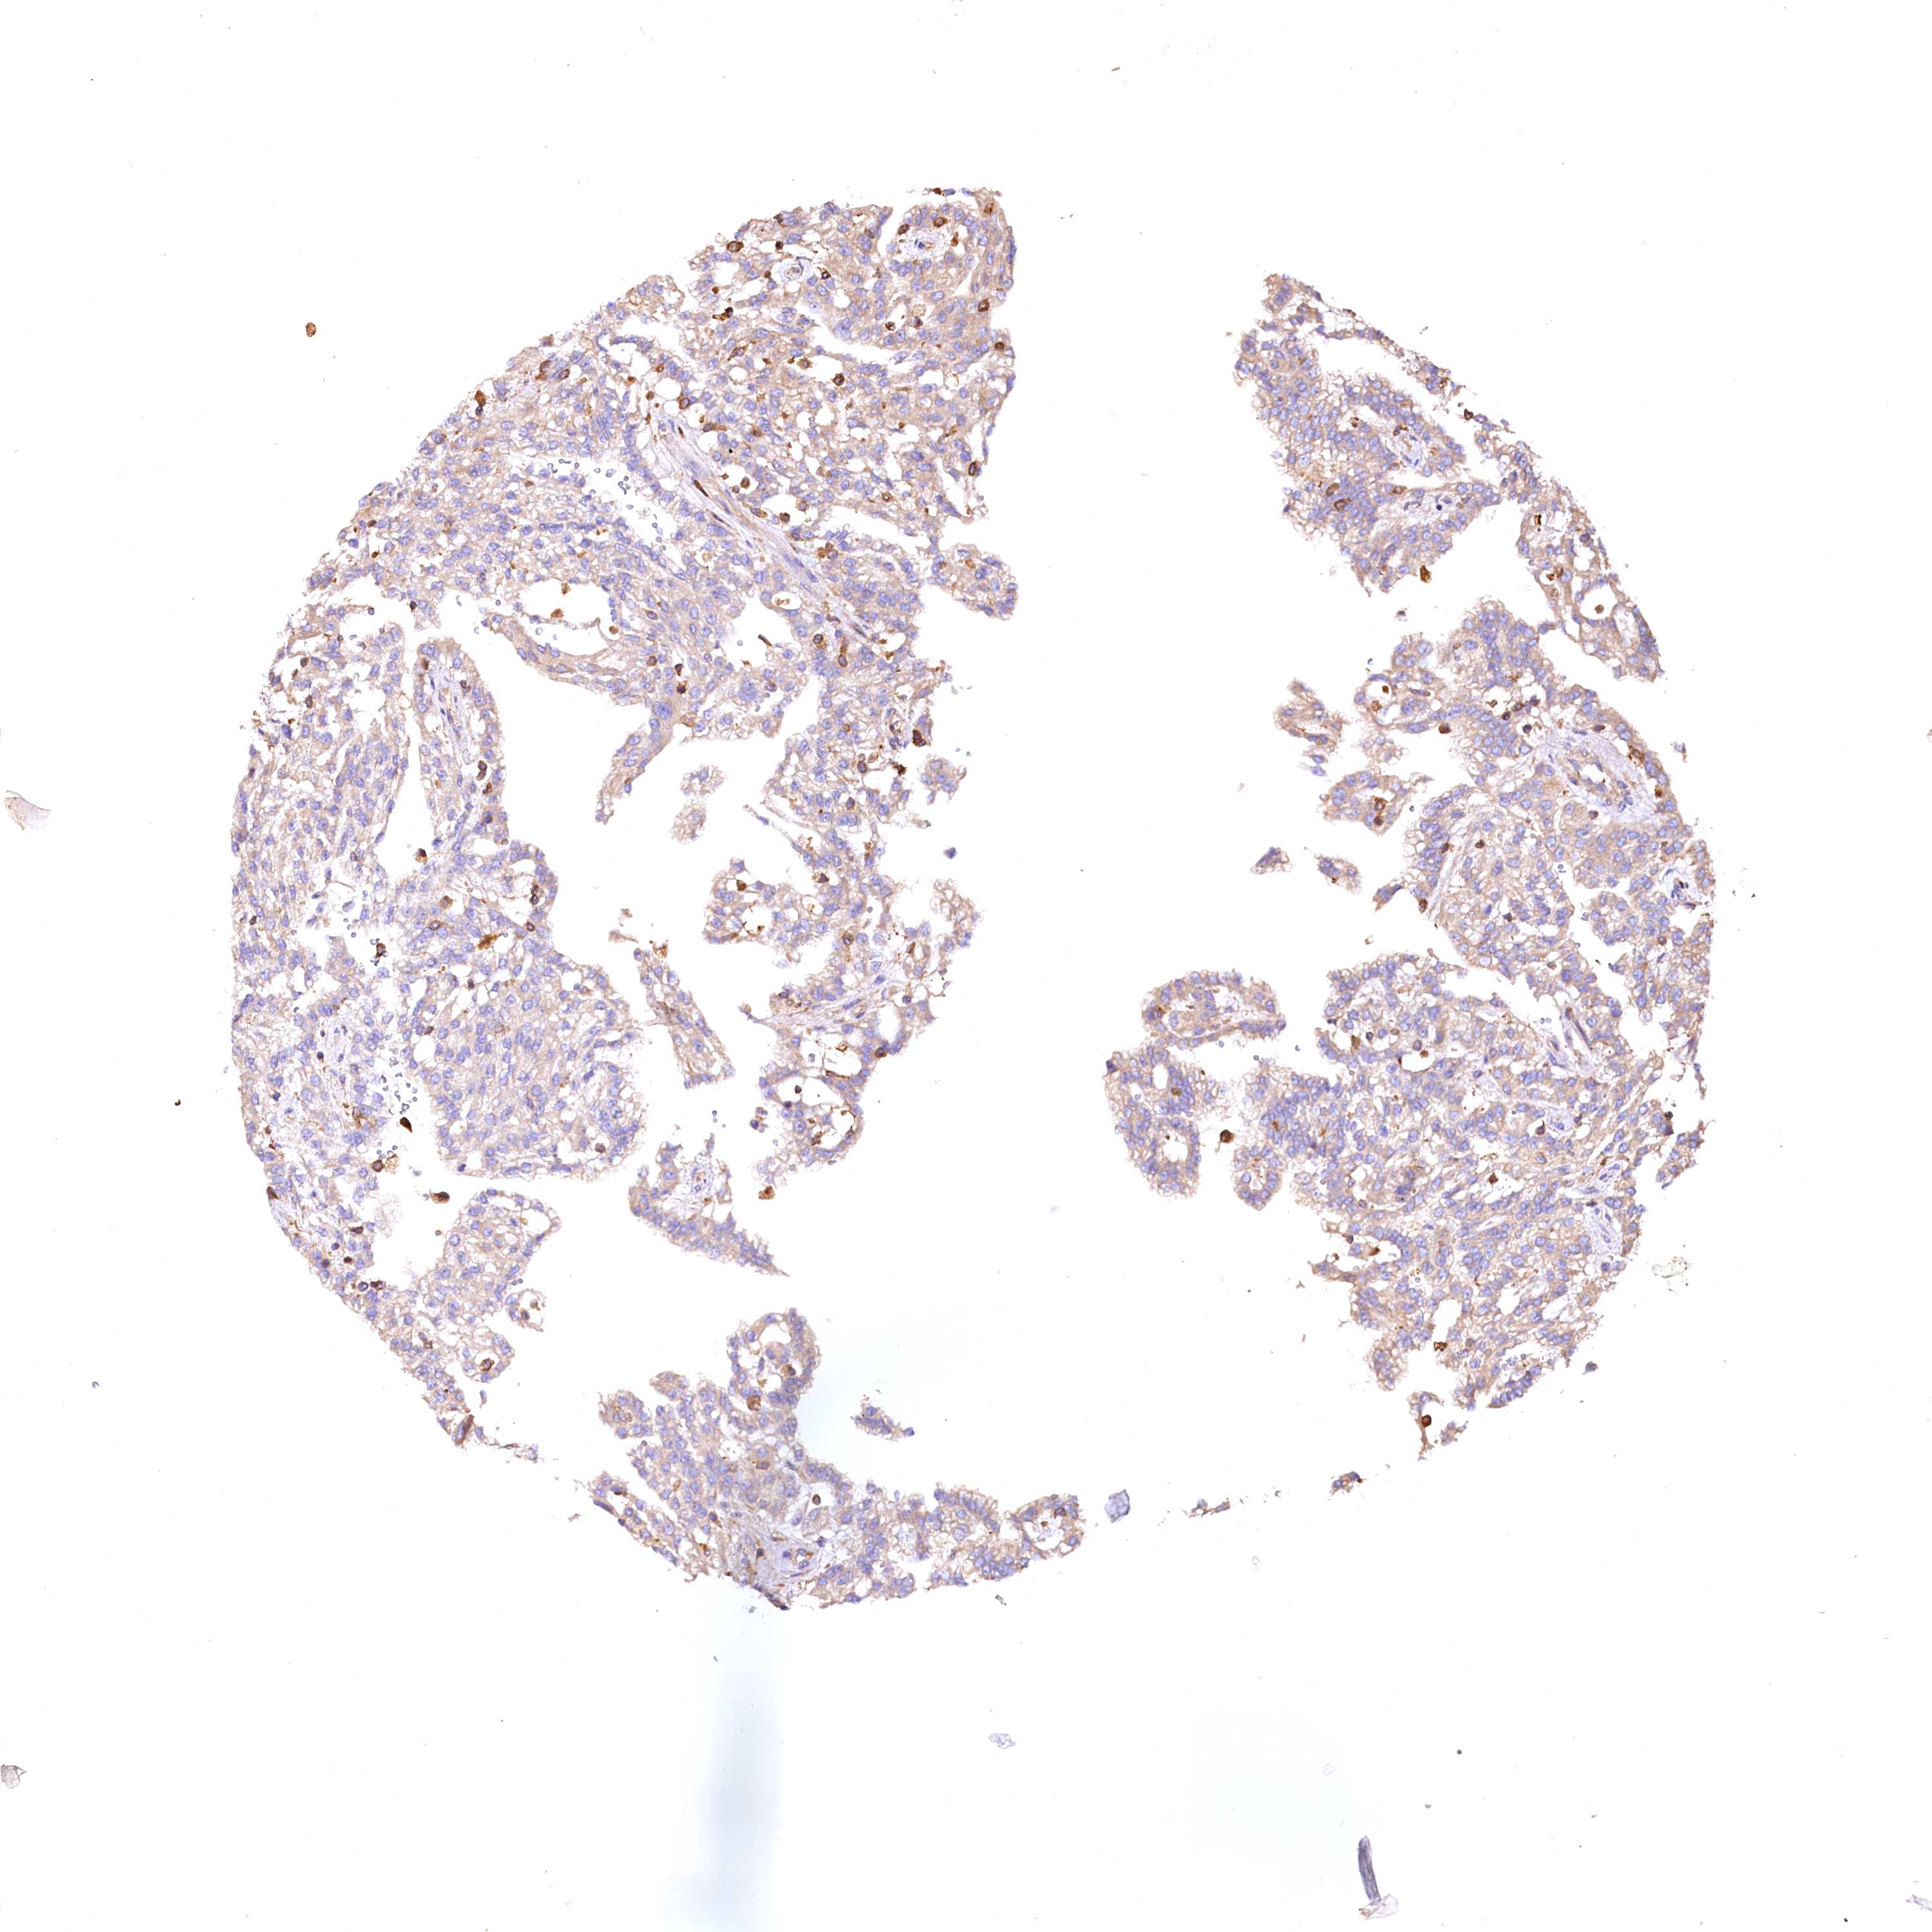

KIDNEY RENAL CLEAR CELL CARCINOMA (VALIDATION) - Interactive survival scatter ploti

The Survival Scatter plot shows the clinical status (i.e. dead or alive) for all individuals in the patient cohort, based on the same data that underlies the corresponding Kaplan-Meier plots. Patients that are alive at last time for follow-up are shown in blue and patients who have died during the study are shown in red.

The x-axis shows the expression levels (FPKM) of the investigated gene in the tumor tissue at the time of diagnosis. The y-axis shows the follow-up time after diagnosis (years). Both axes are complimented with kernel density curves demonstrating the data density over the axes. The top density plot shows the expression levels (FPKM) distribution among dead (red) and alive patients (blue). The right density plot shows the data density of the survived years of dead patients with high and low expression levels respectively, stratified using the cutoff indicated by the vertical dashed line through the Survival Scatter plot. This cutoff is automatically defined based on the FPKM cutoff that minimizes the p-score. The cutoff can be changed by dragging the vertical line or by entering a cutoff value in the square labeled "Current cut-off".

Under the Survival Scatter plot the p-score landscape (black curve; left axis) is shown together with dead median separation (red curve; right axis). Dead median separation is the difference in median mRNA expression between patients who have died with high and low expression, respectively. It is calculated as follows: median FPKM expression of dead patients with high expression - median FPKM expression of dead patients with low expression. This is intended to aid the user in visually exploring custom cutoffs and the associated p-scores and dead median separation.

Individual patient data is displayed and can be filtered by clicking on one or more of the category buttons on the top of the page. Categories describing expression level and patient information include: high, low, alive, dead, female, male and tumor stages. The scale of the x-axis can be toggled between linear and log-scale by clicking on the "x log" button. Mouse-over function shows TCGA ID, patient information and mRNA expression (FPKM) for each patient.

& Survival analysisi

Kaplan-Meier plots summarize results from analysis of correlation between mRNA expression level and patient survival. Patients were divided based on level of expression into one of the two groups "low" (under cut off) or "high" (over cut off). X-axis shows time for survival (years) and y-axis shows the probability of survival, where 1.0 corresponds to 100 percent.

RARS2 is not prognostic in Kidney Renal Clear Cell Carcinoma (validation)

Best expression cut offi

Based on the FPKM value of each gene, patients were classified into two groups and association between prognosis (survival) and gene expression (FPKM) was examined. The best expression cut-off refers the FPKM value that yields maximal difference with regard to survival between the two groups at the lowest log-rank P-value. Best expression cut-off was selected based on survival analysis .

When clicking on this number, the vertical dashed line indicating cut-off, the interactive survival plot, and the Kaplan-Meier curve will be adjusted to show results based on the best expression cut-off.

: 23.23

Median expressioni

Median expression refers to the median FPKM value calculated based on the gene expression (FPKM) data from all patients in this dataset. When clicking on this number, the vertical dashed line indicating cut-off, the interactive survival plot, and the Kaplan-Meier curve will be adjusted to show results based on the median expression.

: N/A

Median follow up timei

Median follow up time refers to the median time (years) after diagnosis with this type of cancer, based on clinical data from all patients in this dataset.

P scorei

Log-rank P value for Kaplan-Meier plot showing results from analysis of correlation between mRNA expression level and patient survival.

N/A

5-year survival highi

5-year survival for patients with higher expression than the expression cutoff.

For melanoma and glioma, 3-year survival is shown.

5-year survival lowi

5-year survival for patients with lower expression than the expression cutoff.

TCGA RNA samplesi

RNA-seq data is reported as average FPKM (number Fragments Per Kilobase of exon per Million reads), generated by the The Cancer Genome Atlas (TCGA) .

Normal distribution across the dataset is visualized with box plots, shown as median and 25th and 75th percentiles. Points are displayed as outliers if they are above or below 1.5 times the interquartile range. FPKM values of the individual samples are presented next to the box plot.

Average pTPM 26.7

Number of samples 100